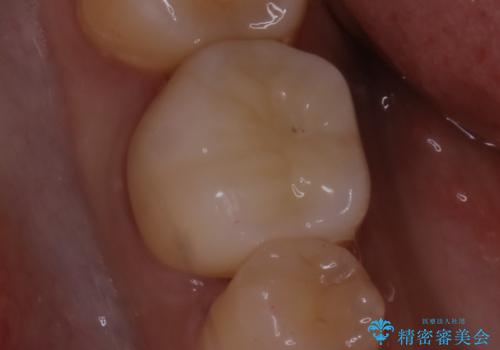

- 銀歯のやり替えをご希望された患者様です。手前の歯にもプラスチックと歯の間に虫歯が出来ていたため、両方とも適合の良いセラミックで補綴しました。

- セラミックインレー7.7万円・仮歯1.1万円・フルジルコニアクラウン7.7万円(税込)費用は治療当時の料金となります

適合不良の補綴物は二次的な虫歯発生のリスクが高まります。

自費診療で用いられる材料は保険適応の材料に比べて、より精密で適合の良い被せ物作ることができるため、長期的な虫歯のリスクを大幅に減らすことが可能です。